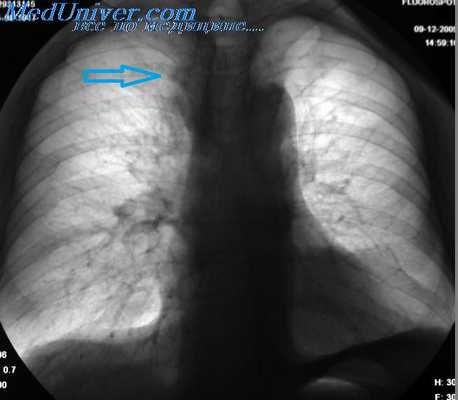

Ателектаз верхней доли правого легкого.

Оцените ниже лежащие изображения, а после продолжите чтение.

- Трехгранное затенение.

- Подъем правого корня легкого

- Облитерация загрудинного пространства (указано стрелкой).

На ПЭТ/КТ визуализируется опухоль легкого с обструкцией правого верхнедолевого бронха, как следствие ателектаз верхний доли правого легкого.

Ниже представлен снимок пациента с туберкулезом, на котором визуализируется ателектаз верхней доли правого легкого, а также обратите внимание на девиацию трахеи.